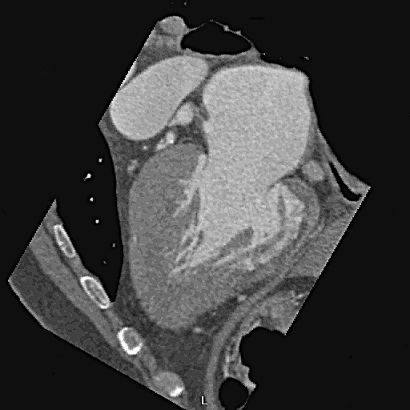

過去冠狀動脈有否狹窄或完全阻塞,最直接、最標準的工具就是心導管,但心導管屬侵入性。近年來影像醫學的發展一日千里,運用非侵入性的電腦斷層(CT)偵測心臟血管疾病,在診斷及預防的重要性愈來愈高,像是冠狀動脈狹窄、主動脈瘤或心肌肥大(圖2)等,都可事先偵測出來,進而達到早期預防或治療的目的。2016年,英國衛生機構NICE更新健康照顧準則,即在未確診為冠心病前的任何形式胸痛,如有異常的靜態心電圖,CCTA都應為第一選擇的檢查工具。

圖2:54歲男性,2006年64切CCTA顯示,心室為黑桃A外型,心肌心室間隔最厚處25.1 mm,近心尖處心肌厚度18.4 mm~20.4 mm(超過15 mm即可考慮為心肌肥大)。此例為典型心尖型心肌肥大,東方人較多。